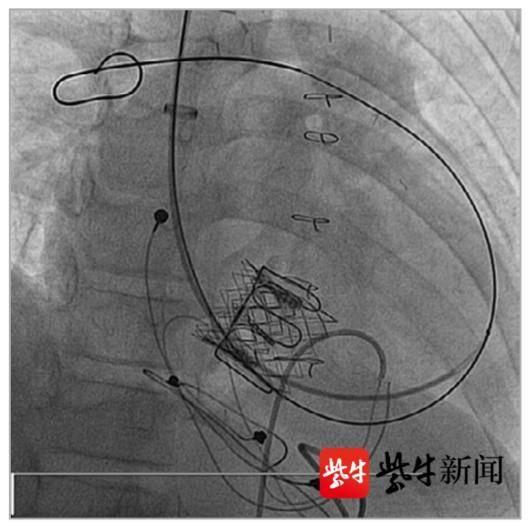

使用球囊扩开衰败的瓣膜 。

在原瓣膜内部置入一枚新瓣 。

据邵永丰主任介绍 , 传统生物瓣需要保存在戊二醛固定液内 , 而范先生使用的新一代瓣膜采用特殊的甘油化处理技术来保持瓣叶组织湿润完整 , 无需保存在固定液内 , 从而得名“干瓣” 。 “这种处理大大提高了瓣膜的抗钙化性能和使用寿命 , 最新的COMMENCE研究随访结果显示 , 该瓣膜5年‘零衰败’ 。 ”邵主任同时强调 , 该“干瓣”瓣膜在设计时采用了最新的“可扩展瓣架”技术 , 使得该瓣膜可用于“瓣中瓣”置换 , “也就是说 , 只要这个‘干瓣’大小足够 , 那么在衰败后 , 即可通过微创介入方式 , 在原有瓣环内置入一枚新的生物瓣 , 无需再次开胸手术 。 ”手术当天 , 范先生成功使用了“干瓣”置换“心门” 。